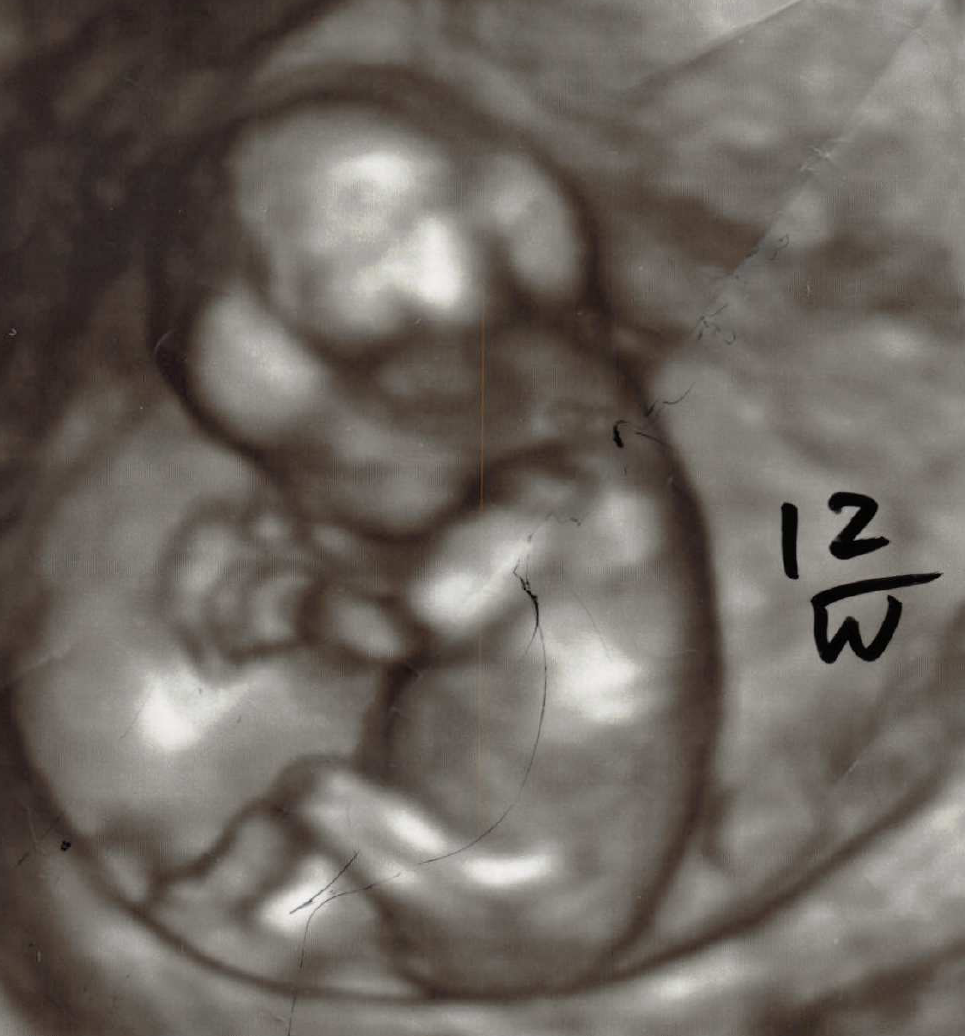

妊娠中どの時期でも、胎児の3D,4Dを見ることができます。

妊娠6か月位迄は、胎児の全身が3D,4Dの画面に入りますが、それ以降になると胎児が大きくなるので全身は入らなくなります。体の部分部分を診たり録画することになります。